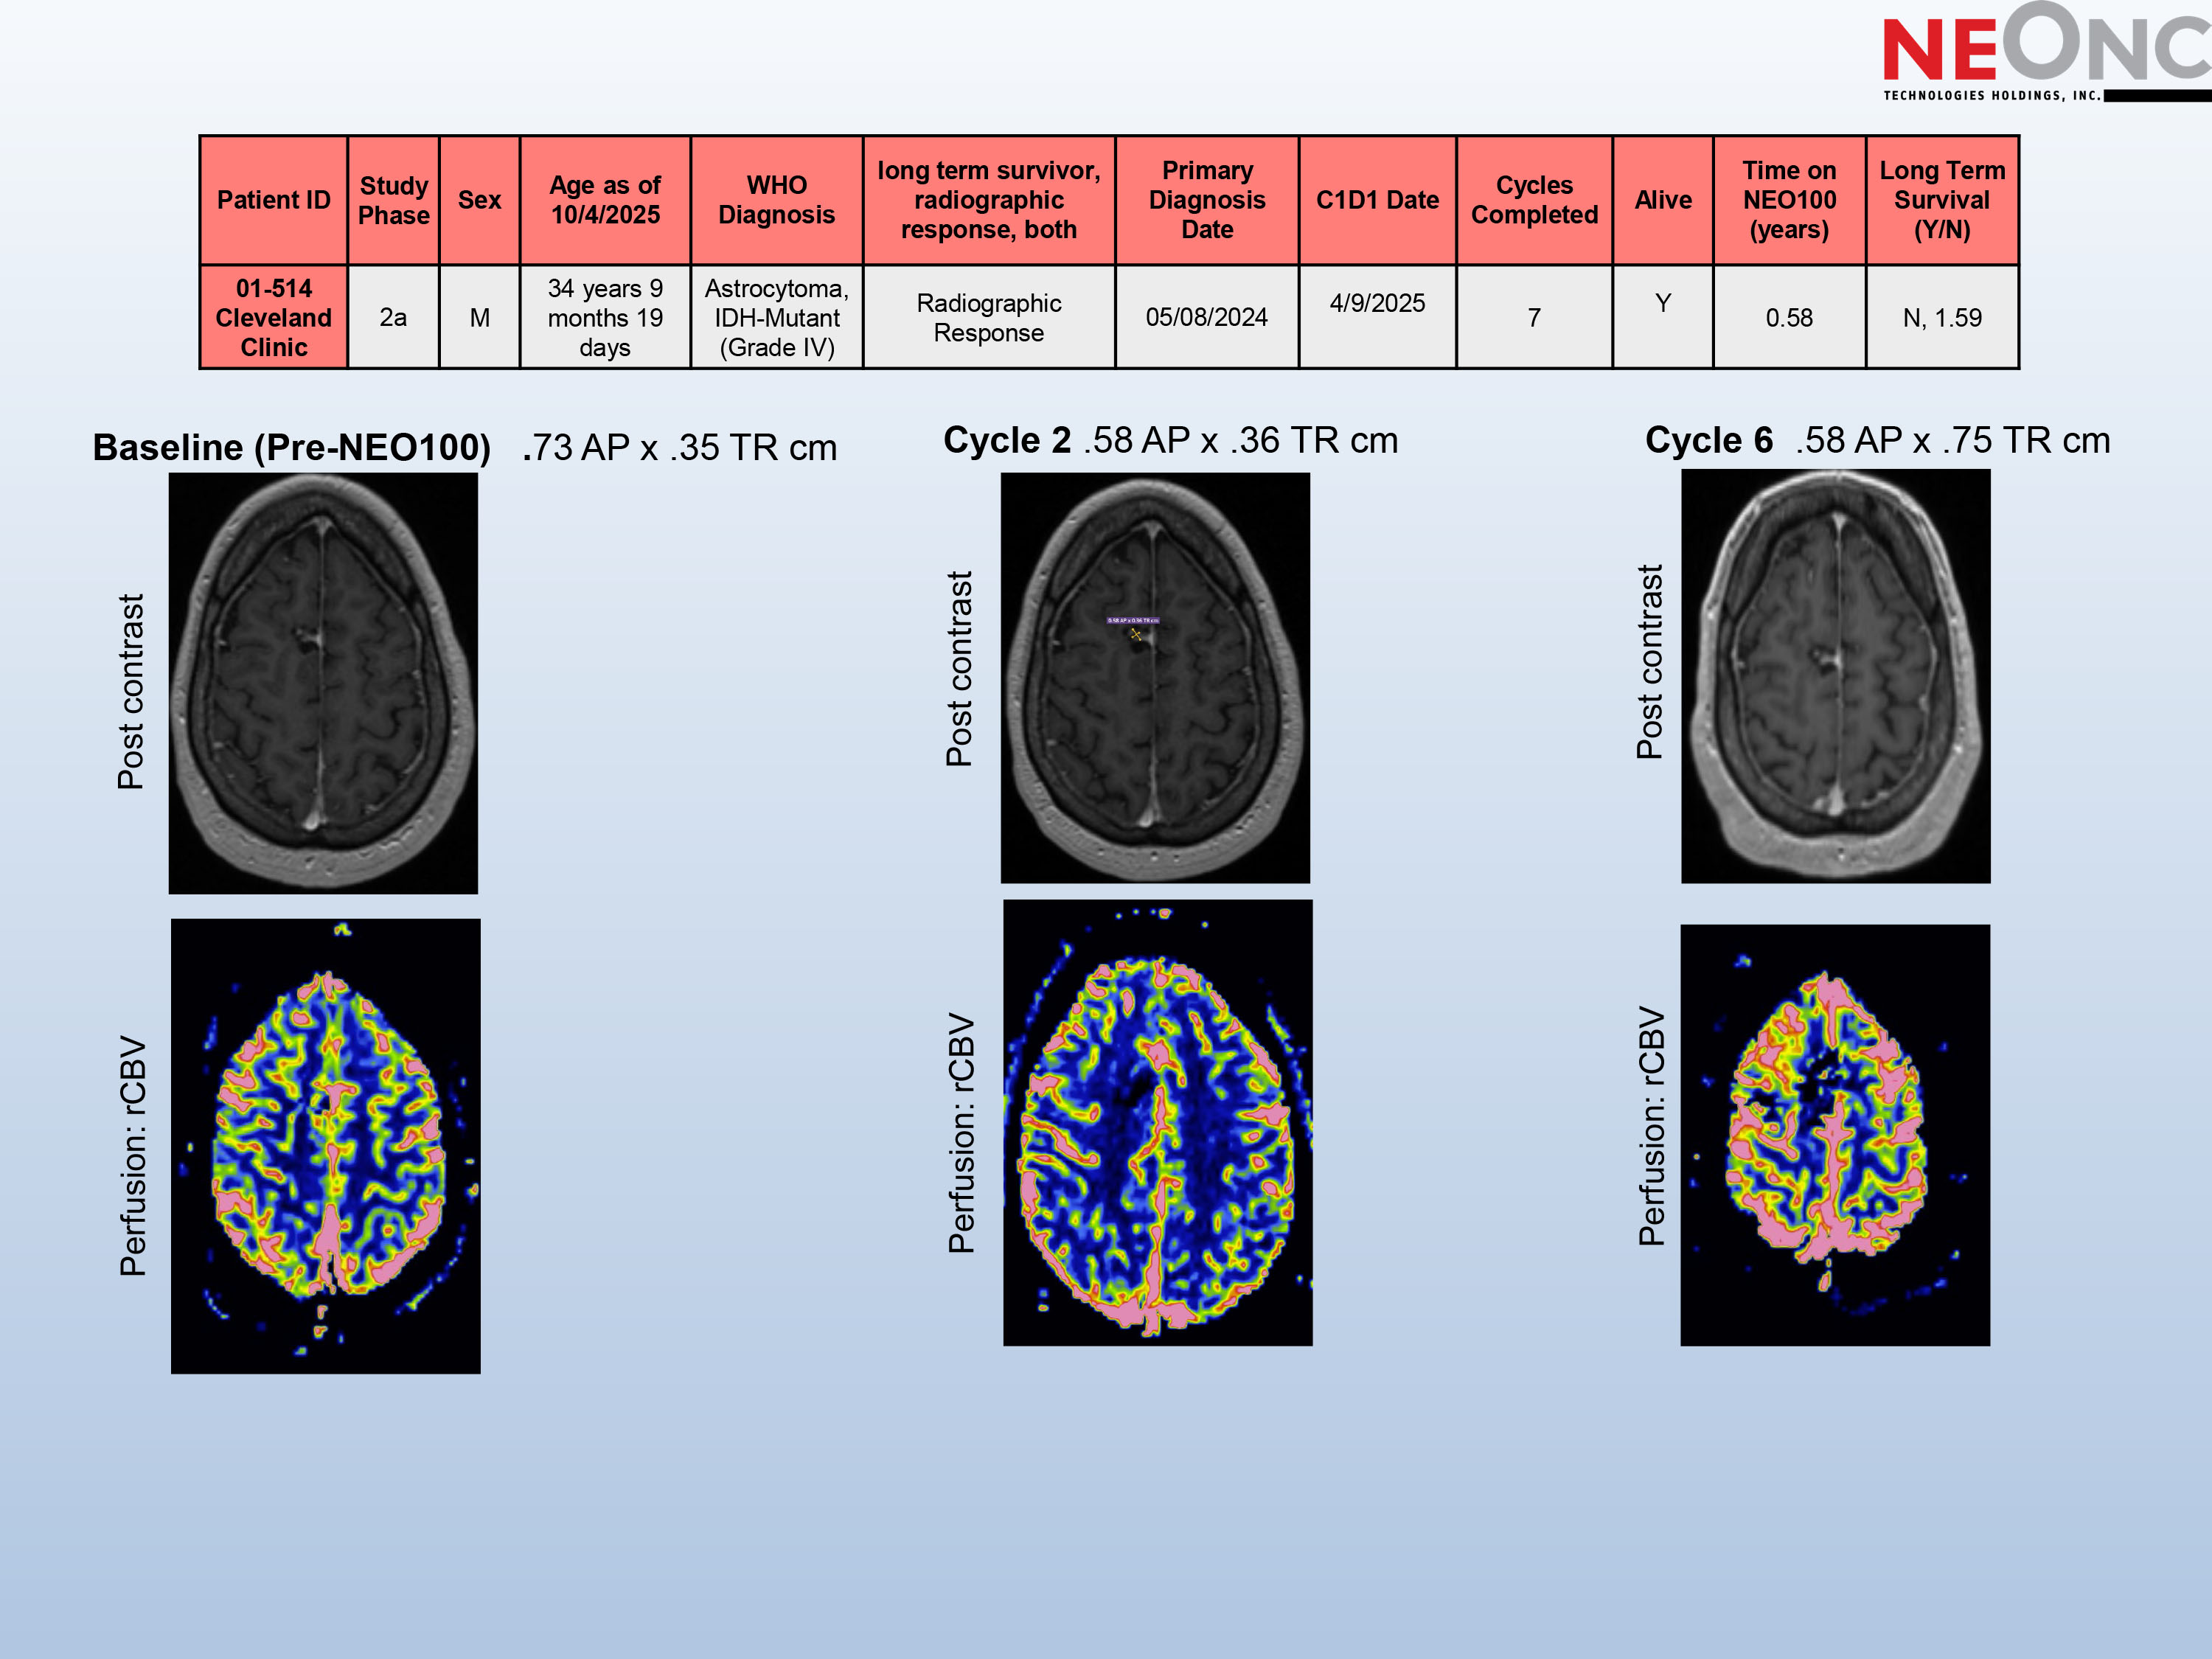

• Diagnosis: WHO Grade IV IDH1 - mutant Astrocytoma , MGMT - unmethylated , • Initial Management: Underwent surgical resection on 08 May 2024 • Adjuvant Therapy: • Radiation therapy: 24 Jun 2024 – 05 Aug 2024 • Temozolomide: 02 Sep 2024 – 13 Jan 2025 • Screening MRI: 31 Mar 2025 • Clinical Trial Enrollment: Initiated NEO100 study; first dose administered on 09 Apr 2025 • Other Therapy: No other anti - tumor treatment received while on NEO100 study Long Term Survival (Y/N) Time on NEO100 (years) Alive Cycles Completed C1D1 Date Primary Diagnosis Date long term survivor, radiographic response, both WHO Diagnosis Age as of 10/4/2025 Sex Study Phase Patient ID N, 1.59 0.58 Y 7 4/9/2025 05/08/2024 Radiographic Response Astrocytoma, IDH - Mutant (Grade IV) 34 years 9 months 19 days M 2a 01 - 514 Cleveland Clinic

Baseline (Pre - NEO100) . 73 AP x .35 TR cm Cycle 2 .58 AP x .36 TR cm Cycle 6 .58 AP x .75 TR cm Long Term Survival (Y/N) Time on NEO100 (years) Alive Cycles Completed C1D1 Date Primary Diagnosis Date long term survivor, radiographic response, both WHO Diagnosis Age as of 10/4/2025 Sex Study Phase Patient ID N, 1.59 0.58 Y 7 4/9/2025 05/08/2024 Radiographic Response Astrocytoma, IDH - Mutant (Grade IV) 34 years 9 months 19 days M 2a 01 - 514 Cleveland Clinic Post contrast Perfusion: rCBV Post contrast Perfusion: rCBV Post contrast Perfusion: rCBV